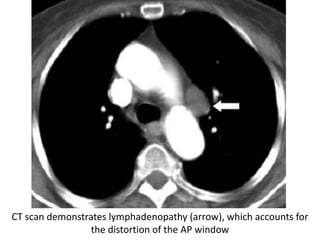

CT scan demonstrates lymphadenopathy (arrow), which accounts for

the distortion of the AP window

CT scan demonstrateslymphadenopathy (arrow), which accounts for the distortion of the AP window